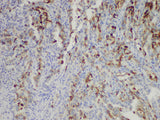

| Reactivity | Human |

| Applications | IHC-P |

| Tissue Specificity | Colon cancer |

Cox-2 is an inducible enzyme which can be involved in the cell reactions of growth factors, tumor promoters and cytokines, all of those factors can induce cox-2 overexpression. Cox-2 is also involved in the synthesis of prostaglandins. Cox-2 expression is significantly increased in 85-90% in colorectal adenocarcinoma patients, while cox-1 expression is unchanged.